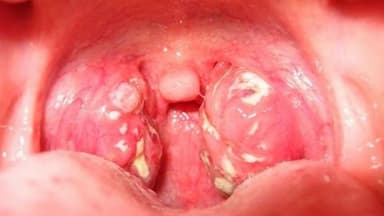

Khi thăm khám sẽ thấy amidan một bên sưng to, đỏ, bề mặt amidan có mủ trắng nhưng dễ lấy bỏ. Phần trước của amidan căng phồng, niêm mạc phù nề. Amidan bị đẩy lệch vào trong và ra sau hoặc ra trước tùy theo thể áp-xe amidan. Lưỡi gà mọng nước, di động kém. Áp-xe amidan thường bị một bên. Hạch cùng bên cũng sưng to, ấn đau do phản ứng viêm lan tới hạch.